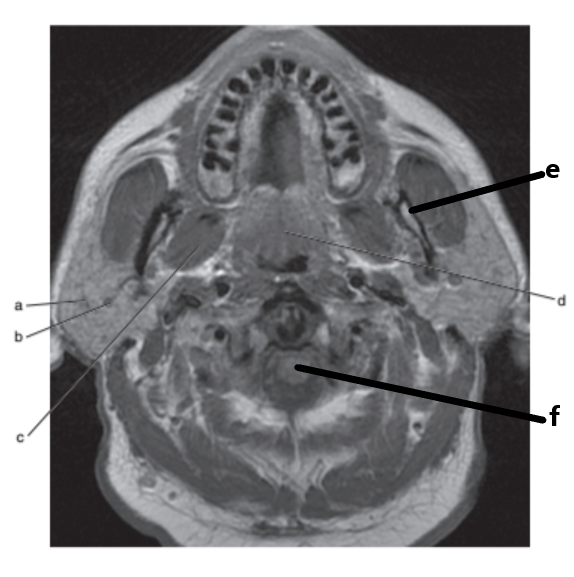

What imaging plane is this ?

transverse

Masseter muscle

What is letter e ?

Submandibular gland

Mandible

Parotid gland